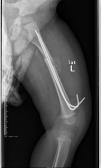

先天性胫骨假关节

肢体短缩延长术,延长9厘米

术前 手术 术后功能恢复良好